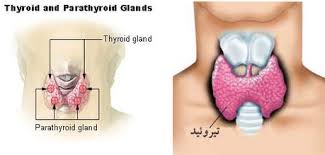

قیمت: 15٬000 تومان - دسته بندی فایل: مباحث رشته هااثرات تیروئید بر هیپوفیز

تحقیق 6 صفحه ای ورد با موضوع اثرات تیروئید بر هیپوفیز

قیمت: 27٬000 تومان - دسته بندی فایل: مباحث رشته هاکمبود هورمون تیروئید-کم کاری تیروئید

غده تیروئید یکی از بزرگترین اعضای اندوکرین است که در افراد بالغ ساکن آمریکای شمالی در حدود 15 تا 20 گرم وزن دارد.